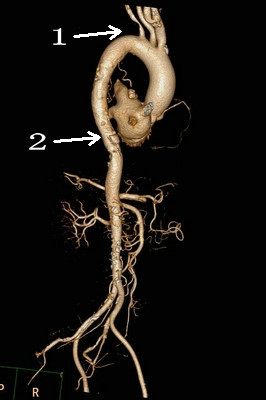

但术前的CTA评估又发现新的问题(图1、2),患者同时合并左侧锁骨下动脉的重度狭窄,狭窄>80%,平素血压多测量右上肢,并未发现,入院测量双上肢血压差别高达30mmHg!更困难的是,主动脉溃疡的破口位于胸10椎体部位,行覆膜支架腔内治疗,患者术后截瘫风险较大。患者病情危重,一旦主动脉破裂出血,死亡率极高!患者家属再次陷入恐慌,在此两难之际,王兵教授果断决策,手术要做,且决定同时介入治疗锁骨下动脉狭窄,因为锁骨下动脉狭窄的解除不仅能改善患者脑部及上肢供血,同时对脊髓供血起到良好的代偿作用,但即便如此,术前也与麻醉科胡强夫主任反复沟通,做好脑脊液穿刺引流准备,最大限度降低截瘫风险。

图1:左侧锁骨下动脉重度狭窄 图2:主动脉透壁性溃疡